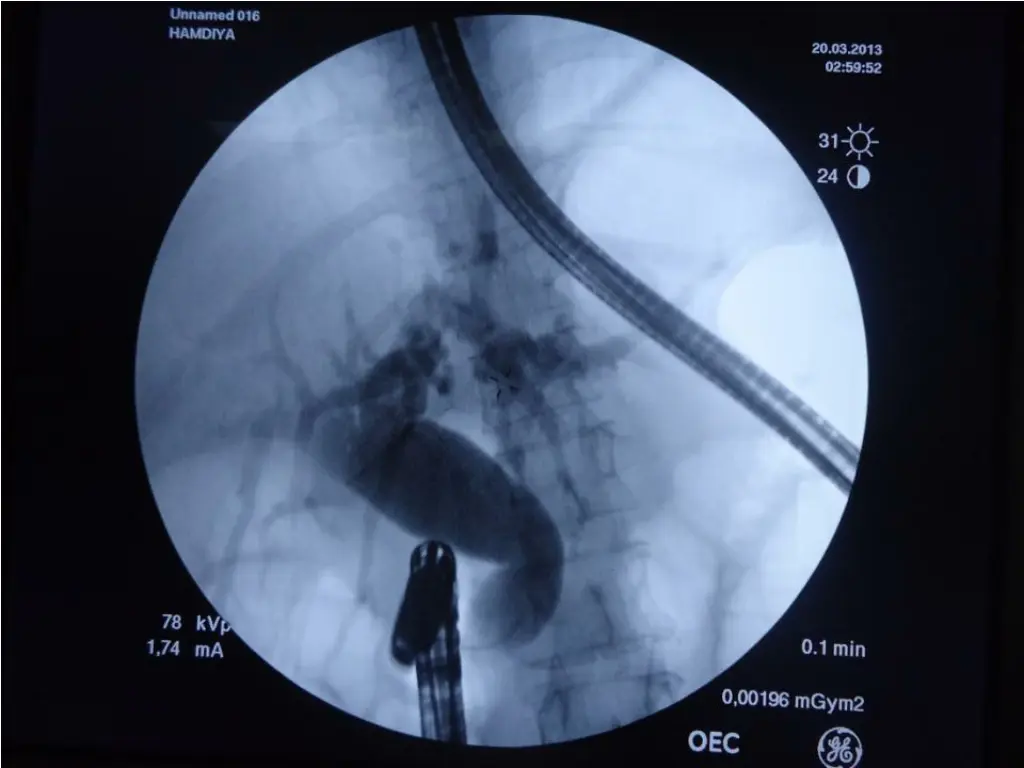

Test Result Hb 12.3 mg/dl WBC 15.3 PLT 654 U/L TSB 30.7 mg/dl D 29.5 mg/dl ALP 243 AST 75 ALT 83